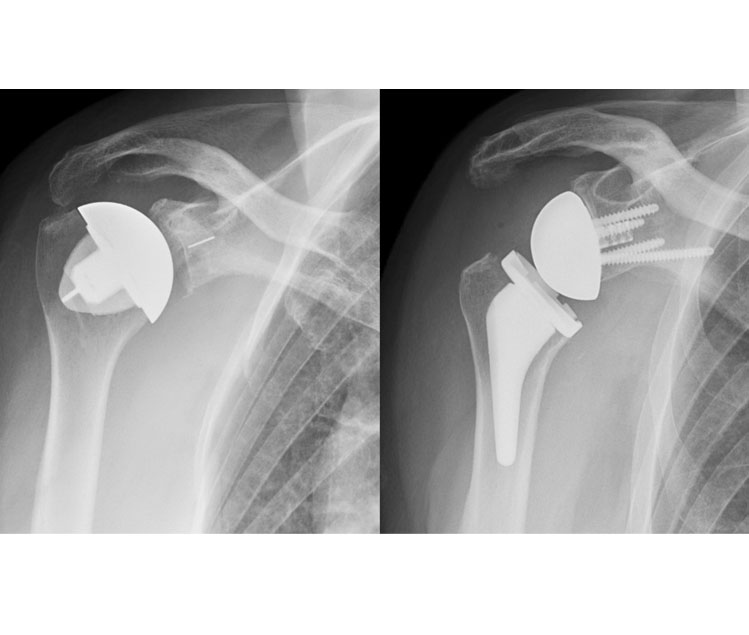

Total & Reverse Shoulder Replacement

Total Shoulder Replacement

A conventional shoulder replacement device mimics the normal anatomy of the shoulder: a plastic "cup" is fitted into the shoulder socket (glenoid), and a metal "ball" is attached to the top of the upper arm bone (humerus). In a reverse total shoulder replacement, the socket and metal ball are switched. The metal ball is fixed to the socket and the plastic cup is fixed to the upper end of the humerus.

Reverse Total Shoulder Replacement

A reverse total shoulder replacement works better for people with cuff tear arthropathy because it relies on different muscles to move the arm. In a healthy shoulder, the rotator cuff muscles help position and power the arm during range of motion. A conventional replacement device also uses the rotator cuff muscles to function properly. In a patient with a large rotator cuff tear and cuff tear arthropathy, these muscles no longer function. The reverse total shoulder replacement relies on the deltoid muscle, instead of the rotator cuff, to power and position the arm.